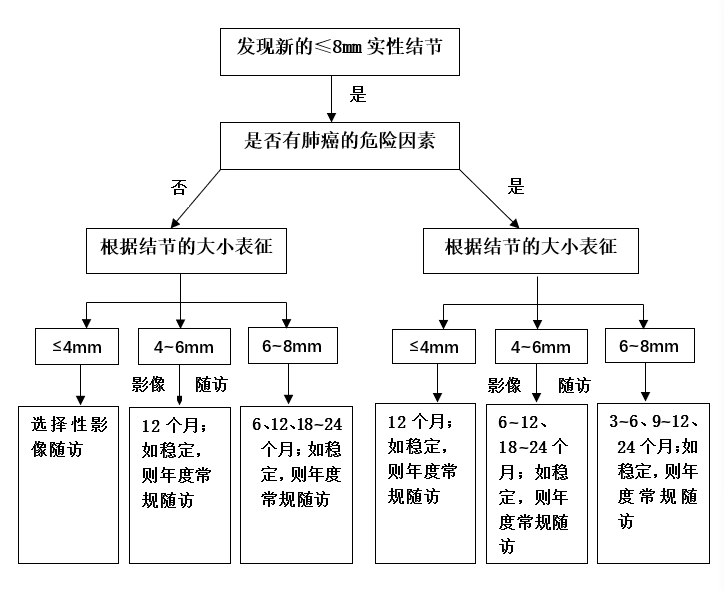

肺结节≤8mm,进一步根据结节大小、恶性肿瘤危险因素决定后续随访时间。≤4mm、4-6mm、6-8mm三个不同大小级别的结节,其初始胸部低剂量CT随访周期不同(见图二),按期随访直至稳定后长期年度常规检查。

图二:直径<8mm实性肺结节的临床管理流程